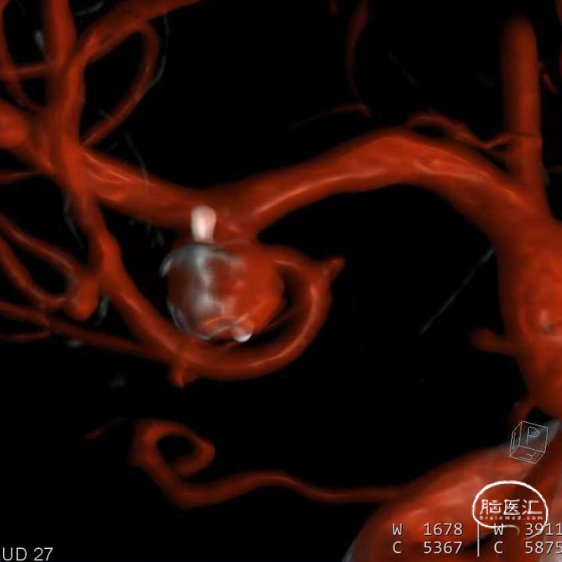

经测量可得动脉瘤宽度平均值为7.28mm,动脉瘤最小高度为4.91mm,参考尺寸选择表,选择WEB™ SL 8*4。

绝对瘤颈宽,右侧P1与瘤颈部分融合,容易疝出从而遮挡P1,应提前进行“分支保护”。

经VIA™微导管推送并释放WEB™ SL 8*4。

6个月后随访,Boss评分0级,动脉瘤完全闭塞不显影,WEB™完全栓塞。